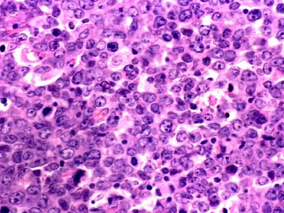

1小时条评论2015年7月,发表于《Blood》的一篇文章考察了复发性T细胞淋巴瘤患者中,mTORC1抑制剂依维莫司的体外及体内抗肿瘤活性。结果显示,依维莫司对于T细胞淋巴瘤细胞具有抗肿瘤活性,并在患者身上产生抗肿瘤效应。 nbsp; 关键点:mTOR通路在TCL细胞中具有结构活性,并负...